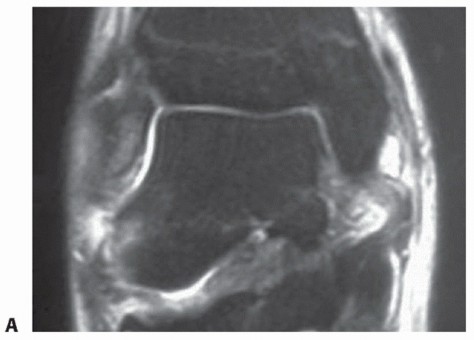

Magnetic resonance (MR) imaging may show an injury to the deltoid ligament (FIG 4), particularly in acute conditions, and it may also reveal pathologic conditions of the posterior tibial tendon.

FIG 4 • Proximal avulsion of the deltoid ligament. AP MR imaging reveals a complete avulsion of the deltoid ligament to the medial malleolus.*